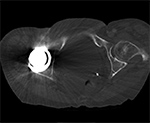

Artifact summation Artifact summation Windowing Windowing

Artifact Summation. (A) Scout image demonstrates bilateral total hip arthroplasties. (B) Axial CT image at the level of acetabular cup and femoral head shows severe transverse streaking related to total summed attenuation of metal components. Optimal Windowing. (A) Axial CT image of the pelvis viewed in soft tissue windows demonstrates extensive streak artifact due to total hip arthroplasty prohibiting evaluation of adjacent bone and soft tissue structure. (B) Same axial CT image set to bone windows results in improved visibility of adjacent bone and soft tissue anatomy.